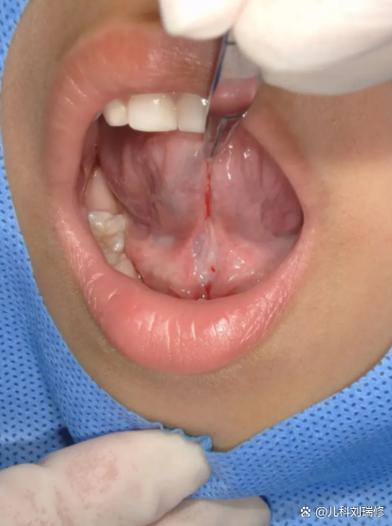

真正的舌系带过短(Ankyloglossia / “短舌筋”)

- 典型表现:

- 舌头无法伸出口唇,或只能伸出一点点,舌尖呈现明显的“W”形或心形。

- 无法用舌头舔到上嘴唇或左右嘴角。

- 怎么办: 如果怀疑是舌系带过短,建议咨询儿科医生或儿童口腔科医生,医生会进行专业评估,如果确实影响了吃奶或发育,可能会建议进行一个简单的小手术(舌系带切开术),这个手术在门诊即可完成,对宝宝影响很小。